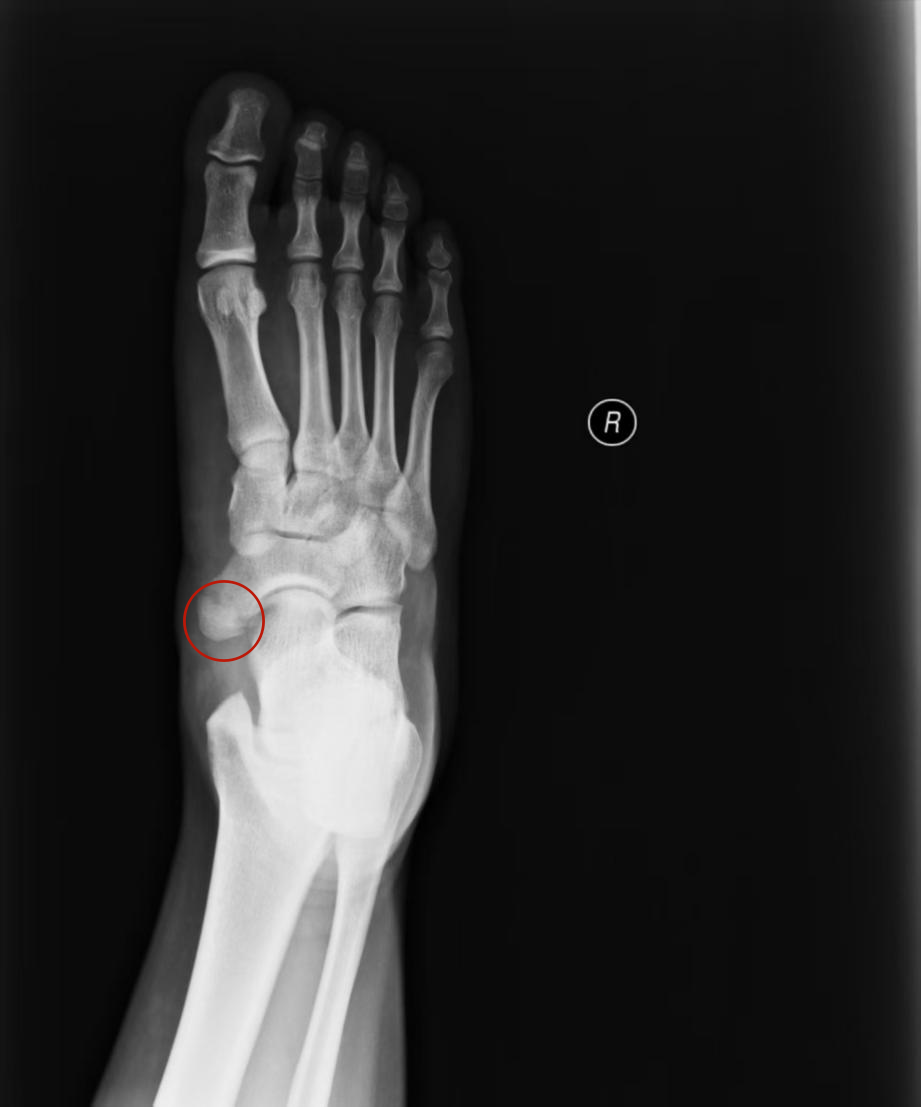

22岁的小秦,曾经是朋友圈里的“活力担当”。但近两年,他足弓内侧那个恼人的肿痛,却像一道无形的枷锁,把奔跑跳跃的快乐越推越远。穿鞋时小心翼翼的试探,走路久了钻心的酸痛,连最爱的运动都成了奢望。辗转尝试过各种药物和支具,效果却时好时坏。直到在威海卫人民医院关节骨病科,副主任丛培阳指着他足部的X光片清晰指出:“这是副舟骨在‘抗议’,保守治疗无效的情况下,微创切除手术能帮你解决问题。”

影像学证据:足部X光片是基础,能清晰显示副舟骨的存在、大小、形态及其与主舟骨的关系。MRI 则能进一步评估胫后肌腱及周围软组织的损伤、炎症水肿程度,为制定治疗方案提供关键依据。